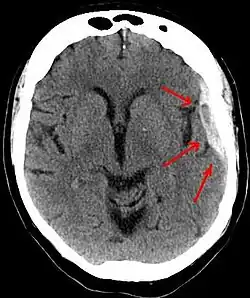

Subdural hematoma as marked by the arrow with significant midline shift | |

A person must receive medical assessment, including a complete neurological examination, after any head trauma. A CT scan or MRI scan will usually detect significant subdural hematomas.

Subdural hematomas occur most often around the tops and sides of the frontal and parietal lobes.[3][2] They also occur in the posterior cranial fossa, and near the falx cerebri and tentorium cerebelli.[3] Unlike epidural hematomas, which cannot expand past the sutures of the skull, subdural hematomas can expand along the inside of the skull, creating a concave shape that follows the curve of the brain, stopping only at dural reflections like the tentorium cerebelli and falx cerebri.

On a CT scan, subdural hematomas are classically crescent-shaped, with a concave surface away from the skull. However, they can have a convex appearance, especially in the early stages of bleeding. This may cause difficulty in distinguishing between subdural and epidural hemorrhages. A more reliable indicator of subdural hemorrhage is its involvement of a larger portion of the cerebral hemisphere. Subdural blood can also be seen as a layering density along the tentorium cerebelli. This can be a chronic, stable process, since the feeding system is low-pressure. In such cases, subtle signs of bleeding—such as effacement of sulci or medial displacement of the junction between gray matter and white matter—may be apparent.

Fresh subdural bleeding is hyperdense, but becomes more hypodense over time due to dissolution of cellular elements. After 3–14 days, the bleeding becomes isodense with brain tissue and may therefore be missed.[20] Subsequently, it will become more hypodense than brain tissue.[21]